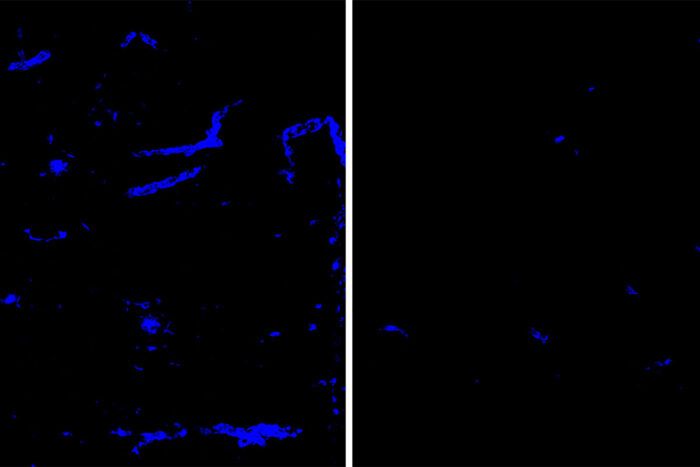

Depositi di amiloide (blu) nel tessuto cerebrale di topo e nei vasi sanguigni vengono ridotti dopo il trattamento con un anticorpo che punta la proteina APOE (a destra), rispetto a un anticorpo placebo (a sinistra).

Gli esperimenti hanno mostrato che con 8 settimane di trattamento con HAE-4, i topi hanno avuto una riduzione delle placche amiloidi nel tessuto cerebrale e nei vasi sanguigni cerebrali. Il trattamento ha anche migliorato significativamente la capacità dei vasi sanguigni del cervello di dilatarsi e restringersi su richiesta, un segno importante di salute vascolare.